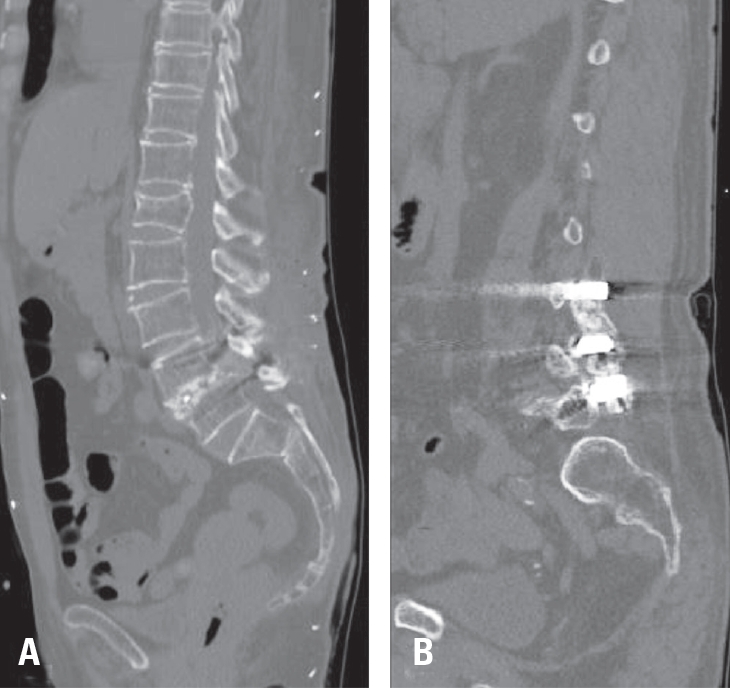

The incidence of mechanical failures was systematically recorded, comparing patients with cement-augmented pedicle screws to those without. Failures were classified into three categories: pull-out, screw loosening, and cage protrusion— the latter defined as displacement of the implanted cage beyond the vertebral body margins (Fig. 3). Fusion status was also evaluated using follow-up radiographs and CT scans. Successful fusion was defined as continuous bone bridging across the intervertebral space without radiolucent lines surrounding the implant. Representative CT images of successful fusion are shown in Fig. 4.

Fig. 4.

Representative computed tomography images of successful spinal fusion. (A) Intervertebral space fusion with continuous bone bridging across the disc space. (B) Posterolateral fusion with bone formation along the posterolateral aspect of the spine.

Fig. 4. Representative computed tomography images of successful spinal fusion. (A) Intervertebral space fusion with continuous bone bridging across the disc space. (B) Posterolateral fusion with bone formation along the posterolateral aspect of the spine.